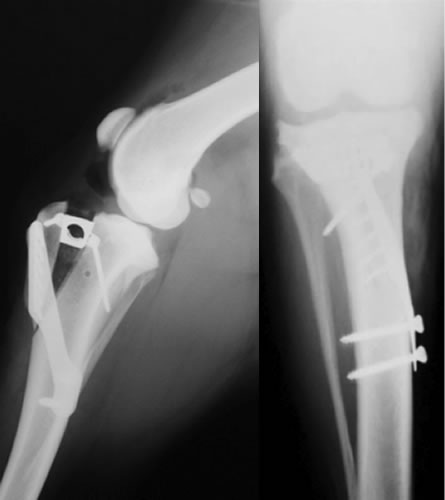

膝蓋骨脱臼グレード4

症状:グレード4になると、重度の跛行を呈することが多くなります。

膝蓋骨脱臼グレード4とは

成長期に膝蓋骨が大腿骨遠位にある滑車溝から脱臼し、大腿骨や脛骨の変形が急速に進行し、膝蓋骨が脱臼し固定されている状態。指で脱臼をなおそうとしても戻らない状態。

外科手術が適応であれば、Block Resectionによる造溝術と脛骨粗面転移術に加え、必要に応じて変形した大腿骨を矯正する骨切り術を同時におこない、膝蓋骨が正しい位置におさまるようアライメントをただします。